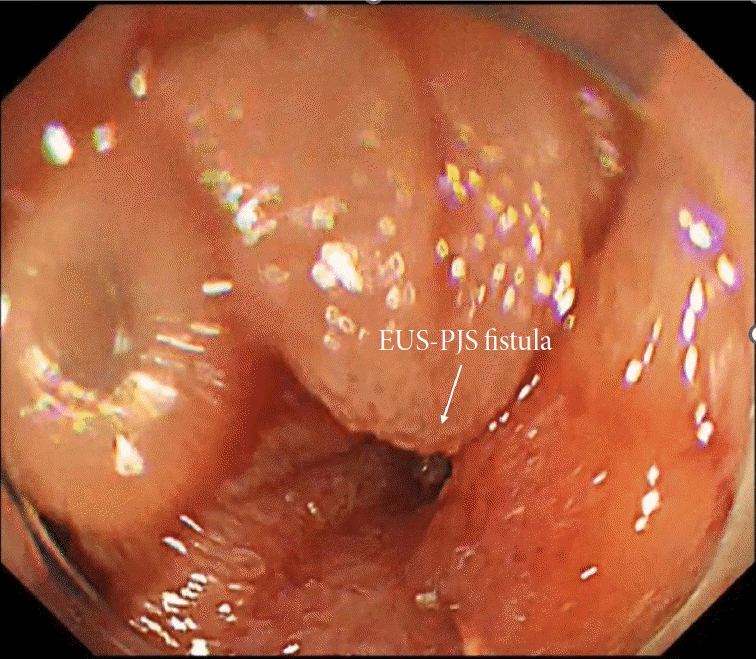

Fig. 5.

Endoscopic view of a widely open pancreaticojejunal anastomosis after stent removal in the endoscopic ultrasound-guided pancreaticojejunostomy (EUS-PJS)